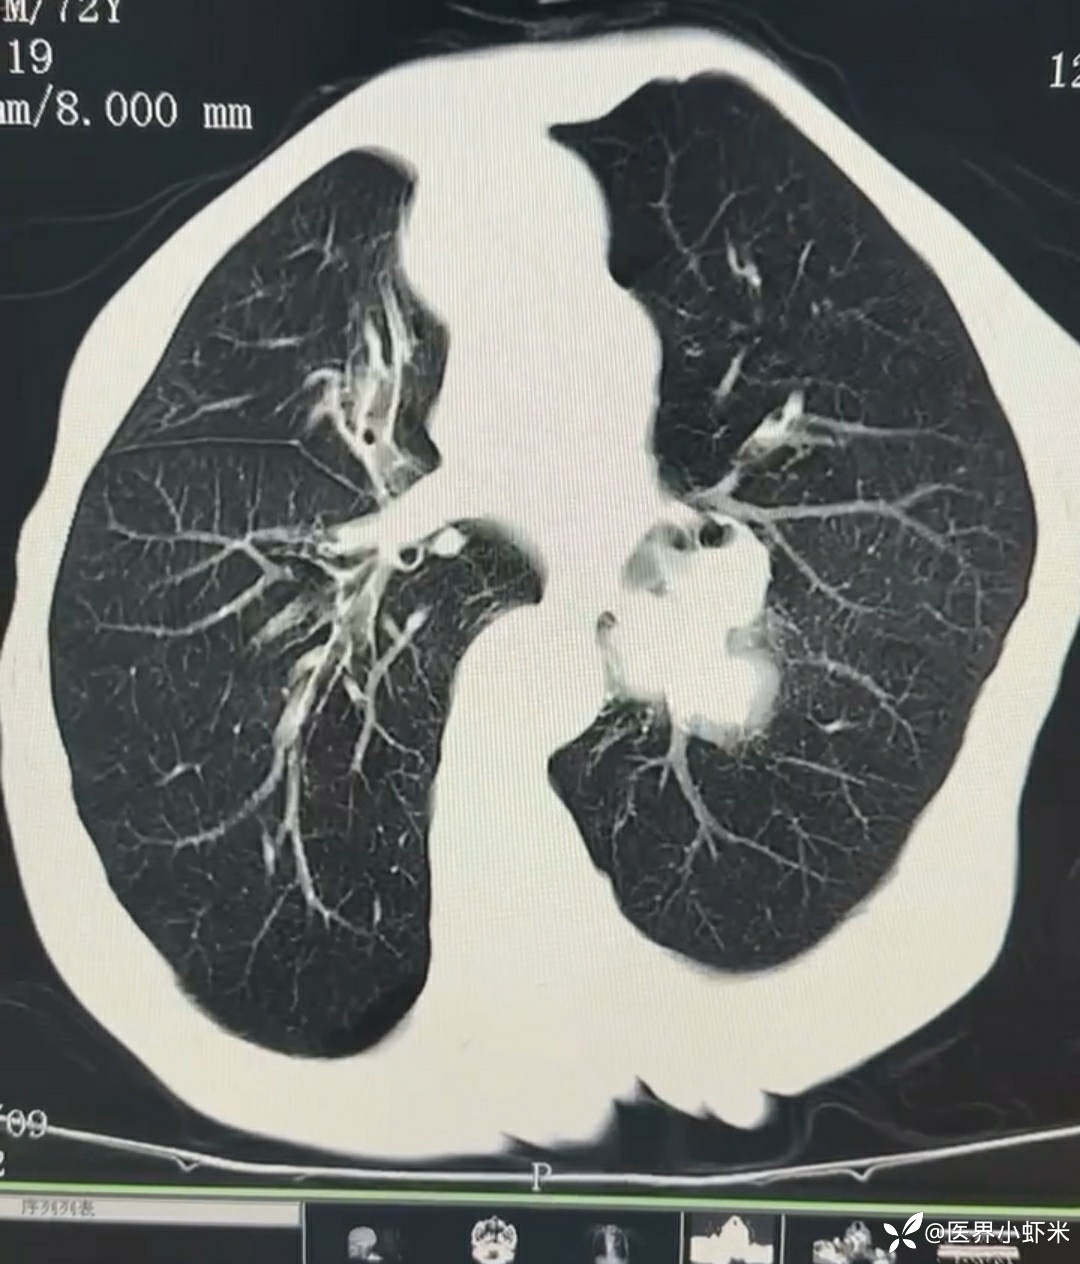

目前考虑:1.中央型肺癌伴2.肝继发恶性肿瘤?2.左丘脑继发恶性肿瘤?3.左丘脑出血?4.肾功能不全5.肝功能异常6右肾萎缩7.肺部感染8.慢性阻塞性肺病7.高血压3级(极高危)。